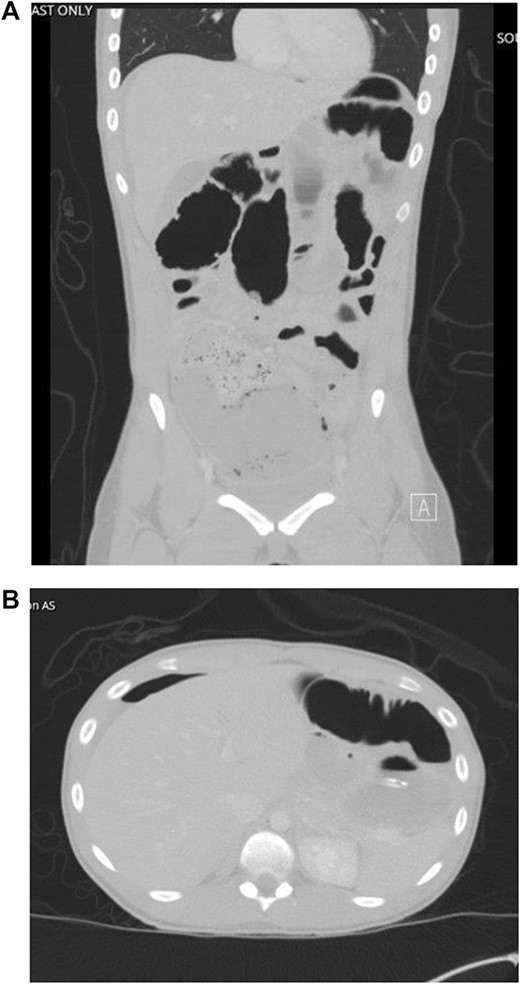

The patient developed abdominal pain with associated leukocytosis with left shift, which prompted a CT of the abdomen and pelvis on postop Day 4 with evidence of moderate to large amount of ascites and a large amount of scattered pneumoperitoneum (Fig. 2).

CT imaging with evidence of ascites and scattered pneumoperitoneum.